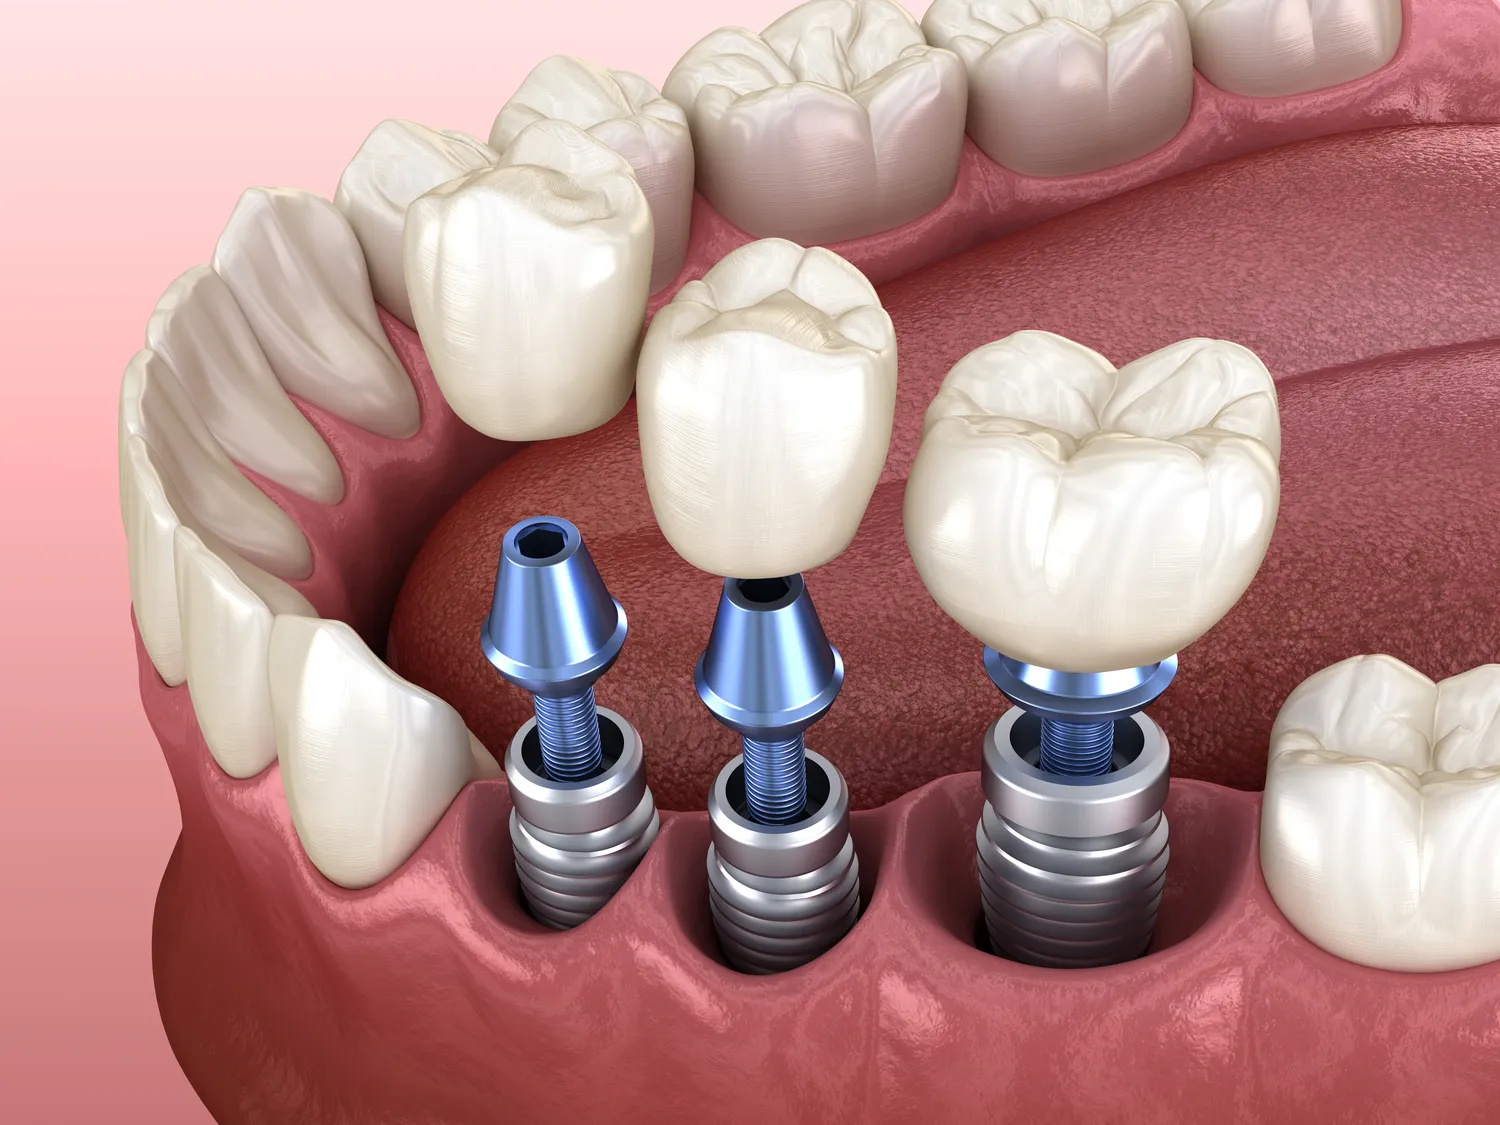

Leczenie kanałowe składa się z kilku kluczowych etapów, które są niezbędne do skutecznego uratowania zęba. Pierwszym krokiem jest dokładna diagnostyka, która zazwyczaj obejmuje wykonanie zdjęcia rentgenowskiego, aby ocenić stan zęba oraz otaczających go tkanek. Na podstawie wyników lekarz podejmuje decyzję o konieczności przeprowadzenia leczenia kanałowego. Kolejnym etapem jest znieczulenie, które ma na celu zapewnienie pacjentowi komfortu podczas zabiegu. Po znieczuleniu dentysta przystępuje do otwarcia korony zęba, aby uzyskać dostęp do kanałów korzeniowych. Następnie lekarz usuwa zakażoną miazgę oraz wszelkie resztki tkankowe, a także dokładnie oczyszcza i dezynfekuje kanały. Po zakończeniu oczyszczania dentysta wypełnia kanały specjalnym materiałem, który zapobiega ponownemu zakażeniu. Ostatnim etapem jest odbudowa korony zęba, co może obejmować założenie wypełnienia lub korony protetycznej, w zależności od stopnia uszkodzenia zęba.

Leczenie kanałowe jest często jedyną opcją ratunkową dla uszkodzonych lub chorych zębów; jednak istnieją pewne alternatywy, które mogą być rozważane w określonych sytuacjach klinicznych. Jedną z takich opcji jest ekstrakcja zęba; w przypadku gdy stan zdrowia zęba jest bardzo poważny lub gdy istnieje ryzyko rozprzestrzenienia się infekcji na inne tkanki jamy ustnej, lekarz może zalecić usunięcie zęba. Choć ekstrakcja może wydawać się prostszym rozwiązaniem, wiąże się z koniecznością późniejszej odbudowy brakującego zęba, co może obejmować zastosowanie mostów protetycznych, implantów lub protez. Inną alternatywą jest leczenie farmakologiczne, które może być stosowane w przypadku mniej zaawansowanych infekcji, jednak nie zawsze jest to wystarczające rozwiązanie. Warto również wspomnieć o nowoczesnych metodach regeneracyjnych, takich jak terapia komórkowa czy zastosowanie biomateriałów, które mogą wspierać proces gojenia i regeneracji tkanek.